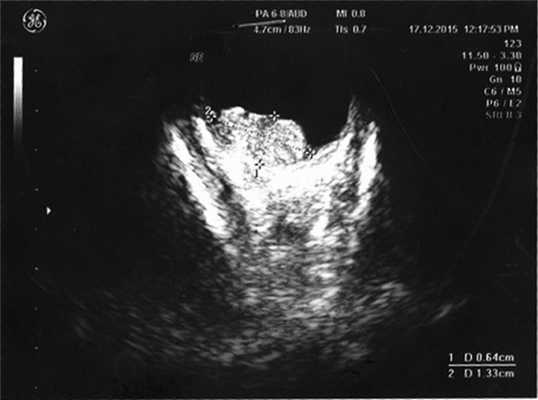

Согласно данным ультразвукового исследования, у заднего полюса выявлены плюс-ткань гетерогенной эхоструктуры с единичными кальцинатами, размером 6,4×13,3 мм, вторичная отслойка сетчатки (рис. 2). Учитывая локализацию опухоли (солитарный опухолевый узел, полностью перекрывающий ДЗН), отсутствие шансов на зрение, размеры образования и высокий риск экстрабульбарного распространения опухоли, выполнена энуклеация левого глаза с пластикой культи. После получения патогистологического заключения (злокачественная медуллоэпителиома) ребенок направлен на консультацию к детскому онкологу с целью возможного выявления новообразования в головном мозге. По данным магнитно-резонансной томографии, опухолевых очагов в ЦНС не выявлено, однако в связи с прорастанием опухоли за laminacribrosa пациенту назначен курс лучевой и химиотерапии (циклофосфан, вепезид, карбоплатин).

Рис. 2. Результат эхографии левого глаза у ребенка с подозрением на монокулярную форму ретинобластомы.

Диагностика внутриглазной медуллоэпителиомы является трудной задачей. Сочетание таких клинических признаков как плотная ретролентальная мембрана, подвывих хрусталика, вторичная гипертензия позволяют заподозрить внутриглазную опухоль. Выявление при ультразвуковом исследовании гетерогенной ткани, включающей анэхогенные зоны, подтверждает наличие медуллоэпителиомы.